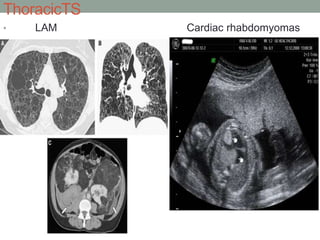

ThoracicTS

• LAM Cardiac rhabdomyomas